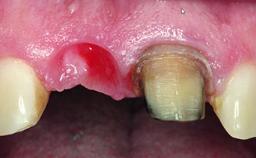

A 32-year-old female Caucasian patient with a compromised maxillary right central incisor was referred to us by a general dentist. Her chief complaints were discomfort and mobility of tooth 11 with unsatisfactory esthetics due to discoloration. The patient reported a previous trauma, some years earlier, as the origin of pathology on the afflicted tooth. Anamnesis was negative for any other dental or periodontal pathology in the remaining dentition. The patient did not take any medication and reported to be a light smoker (5–10 cigs/day). She had high esthetic expectations of her treatment. The extraoral examination revealed a high smile line with full exposure of her maxillary teeth and surrounding soft tissue in the area between the second premolars.

| Soft Tissue Grafting | Staged |